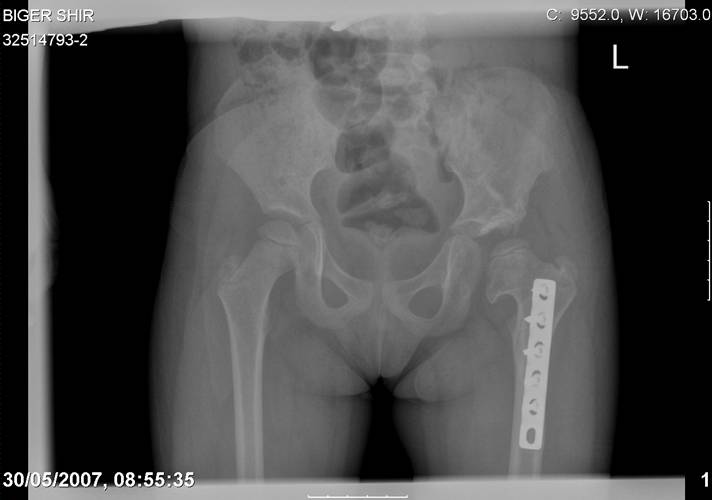

Navernoe Dega

Chto by ne byt goloslovnym posilau vam svoi sluchai gde sdelal vse chto napisal vyshe

Mark Eidelman